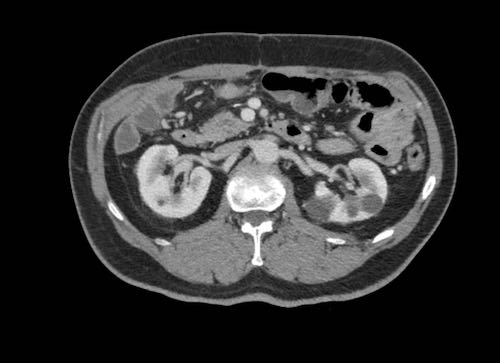

Ca lâm sàng 2

Cuộn qua các lát cắt.

Bạn có thể phát hiện tất cả các tổn thương cấy ghép phúc mạc không?

.jpeg)